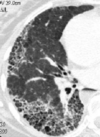

80

Patrón en panal

81

Patrón intersticial bibasal

82